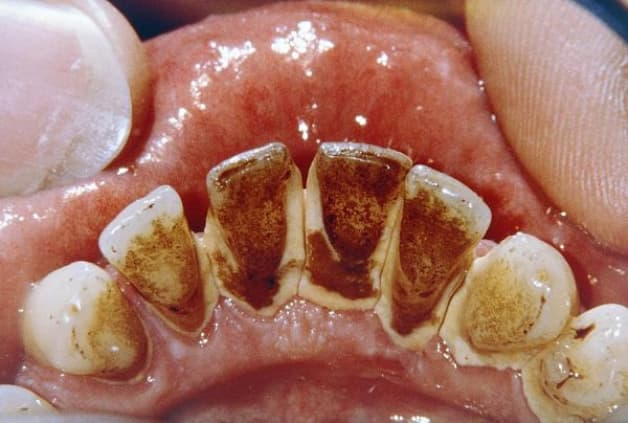

Được mô tả phía trên là cao răng thường. Ngoài chúng, còn một loại cao răng khác nữa, gọi là cao răng huyết thanh. Còn cao răng huyết thanh là cao răng được hình thành như sau: Khi cao răng thường gây viêm lợi, vùng lợi viêm tiết dịch và chảy máu. Dịch viêm và máu này ngấm vào cao răng thường, nhuộm cao răng thường thành màu nâu đỏ. Cao răng nâu đỏ chính là cao răng huyết thanh.

Cao răng nâu đỏ chính là cao răng huyết thanh